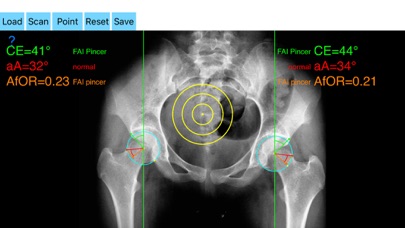

The drawn lines between points, allows app to estimate in radiographs, Center-Edge Angle (CE), α - angle (aA) and the anterior femoral offset ratio (AfOR). The measured values are compared with values from normal reference database. In case the measured angles are beyond the normal range, the hip is categorized as normal, dysplastic, borderline dysplastic hip and the type of femoroacetabular impingement (FAI) deformity namely cam type, pincer type or mixed is printed over the screen accordingly. Measures by the app are not affected by the X-ray projection.